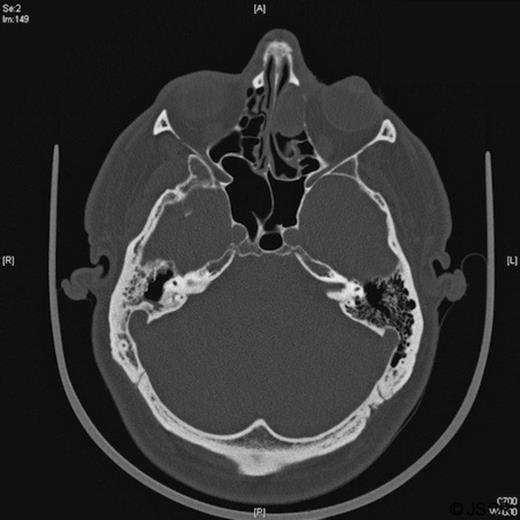

A follow-up MRI scan in 2009 showed contrast-enhancing soft tissue abnormalities within both of the frontal sinuses and the left ethmoid sinus (Figures 1 and 2). A CT scan showed soft tissue abnormalities in these locations (Figure 3). An incisional biopsy confirmed a subepithelial ameloblastoma.